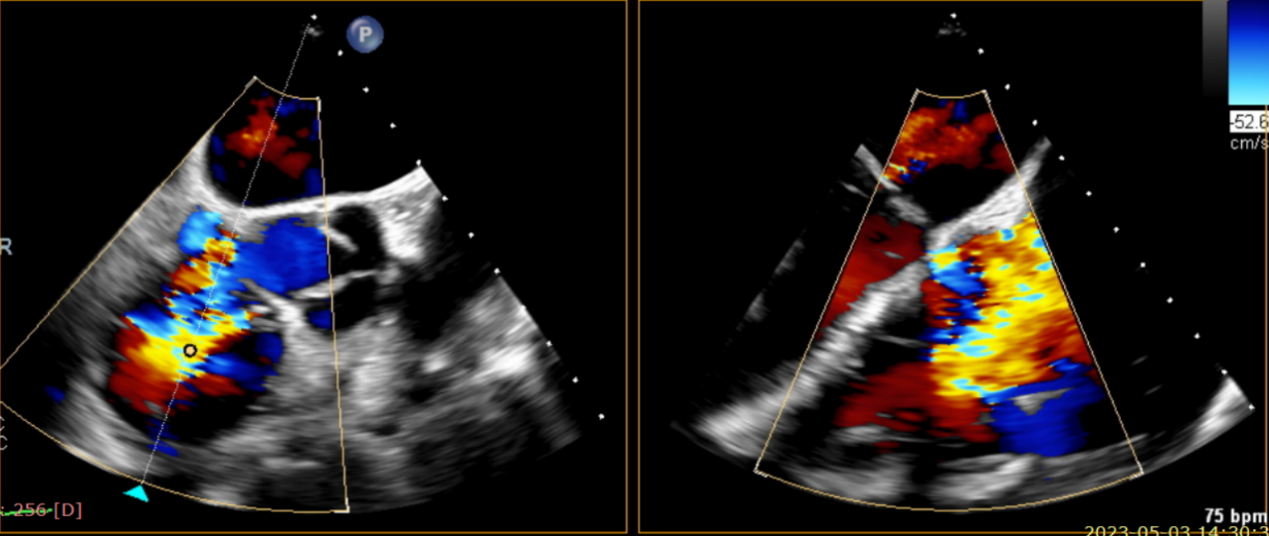

術前超聲提示大量三尖瓣反流